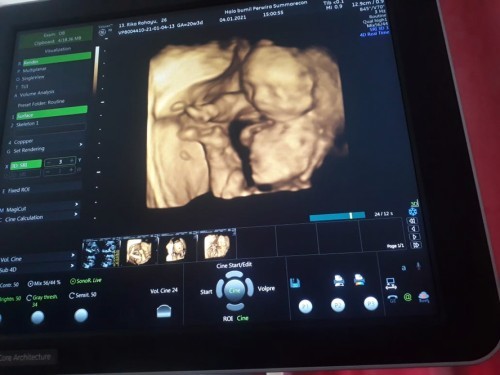

Mohon maaf cuma mau mengungkapkan kebahagiaan ya bunda2 🙏🏻 Subhanallah bahagia nya skrg usia dede di dlm kandungan ibun sudah 21minggu. Gasabar ayah sama ibun mau ketemu kamu. Gerak yg aktif ya nak 😘😘😘 Kalo sudah waktunya lahir kedunia segera ya nak disini ada ayah dan ibun 🥰 #pregnancy #firstbaby #jangandibully